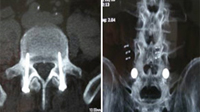

Implante endoscópico en L4/L5 para expandir pinzamientos discales sin

necesidad de recurrir a la cirugía abierta. - Vídeos